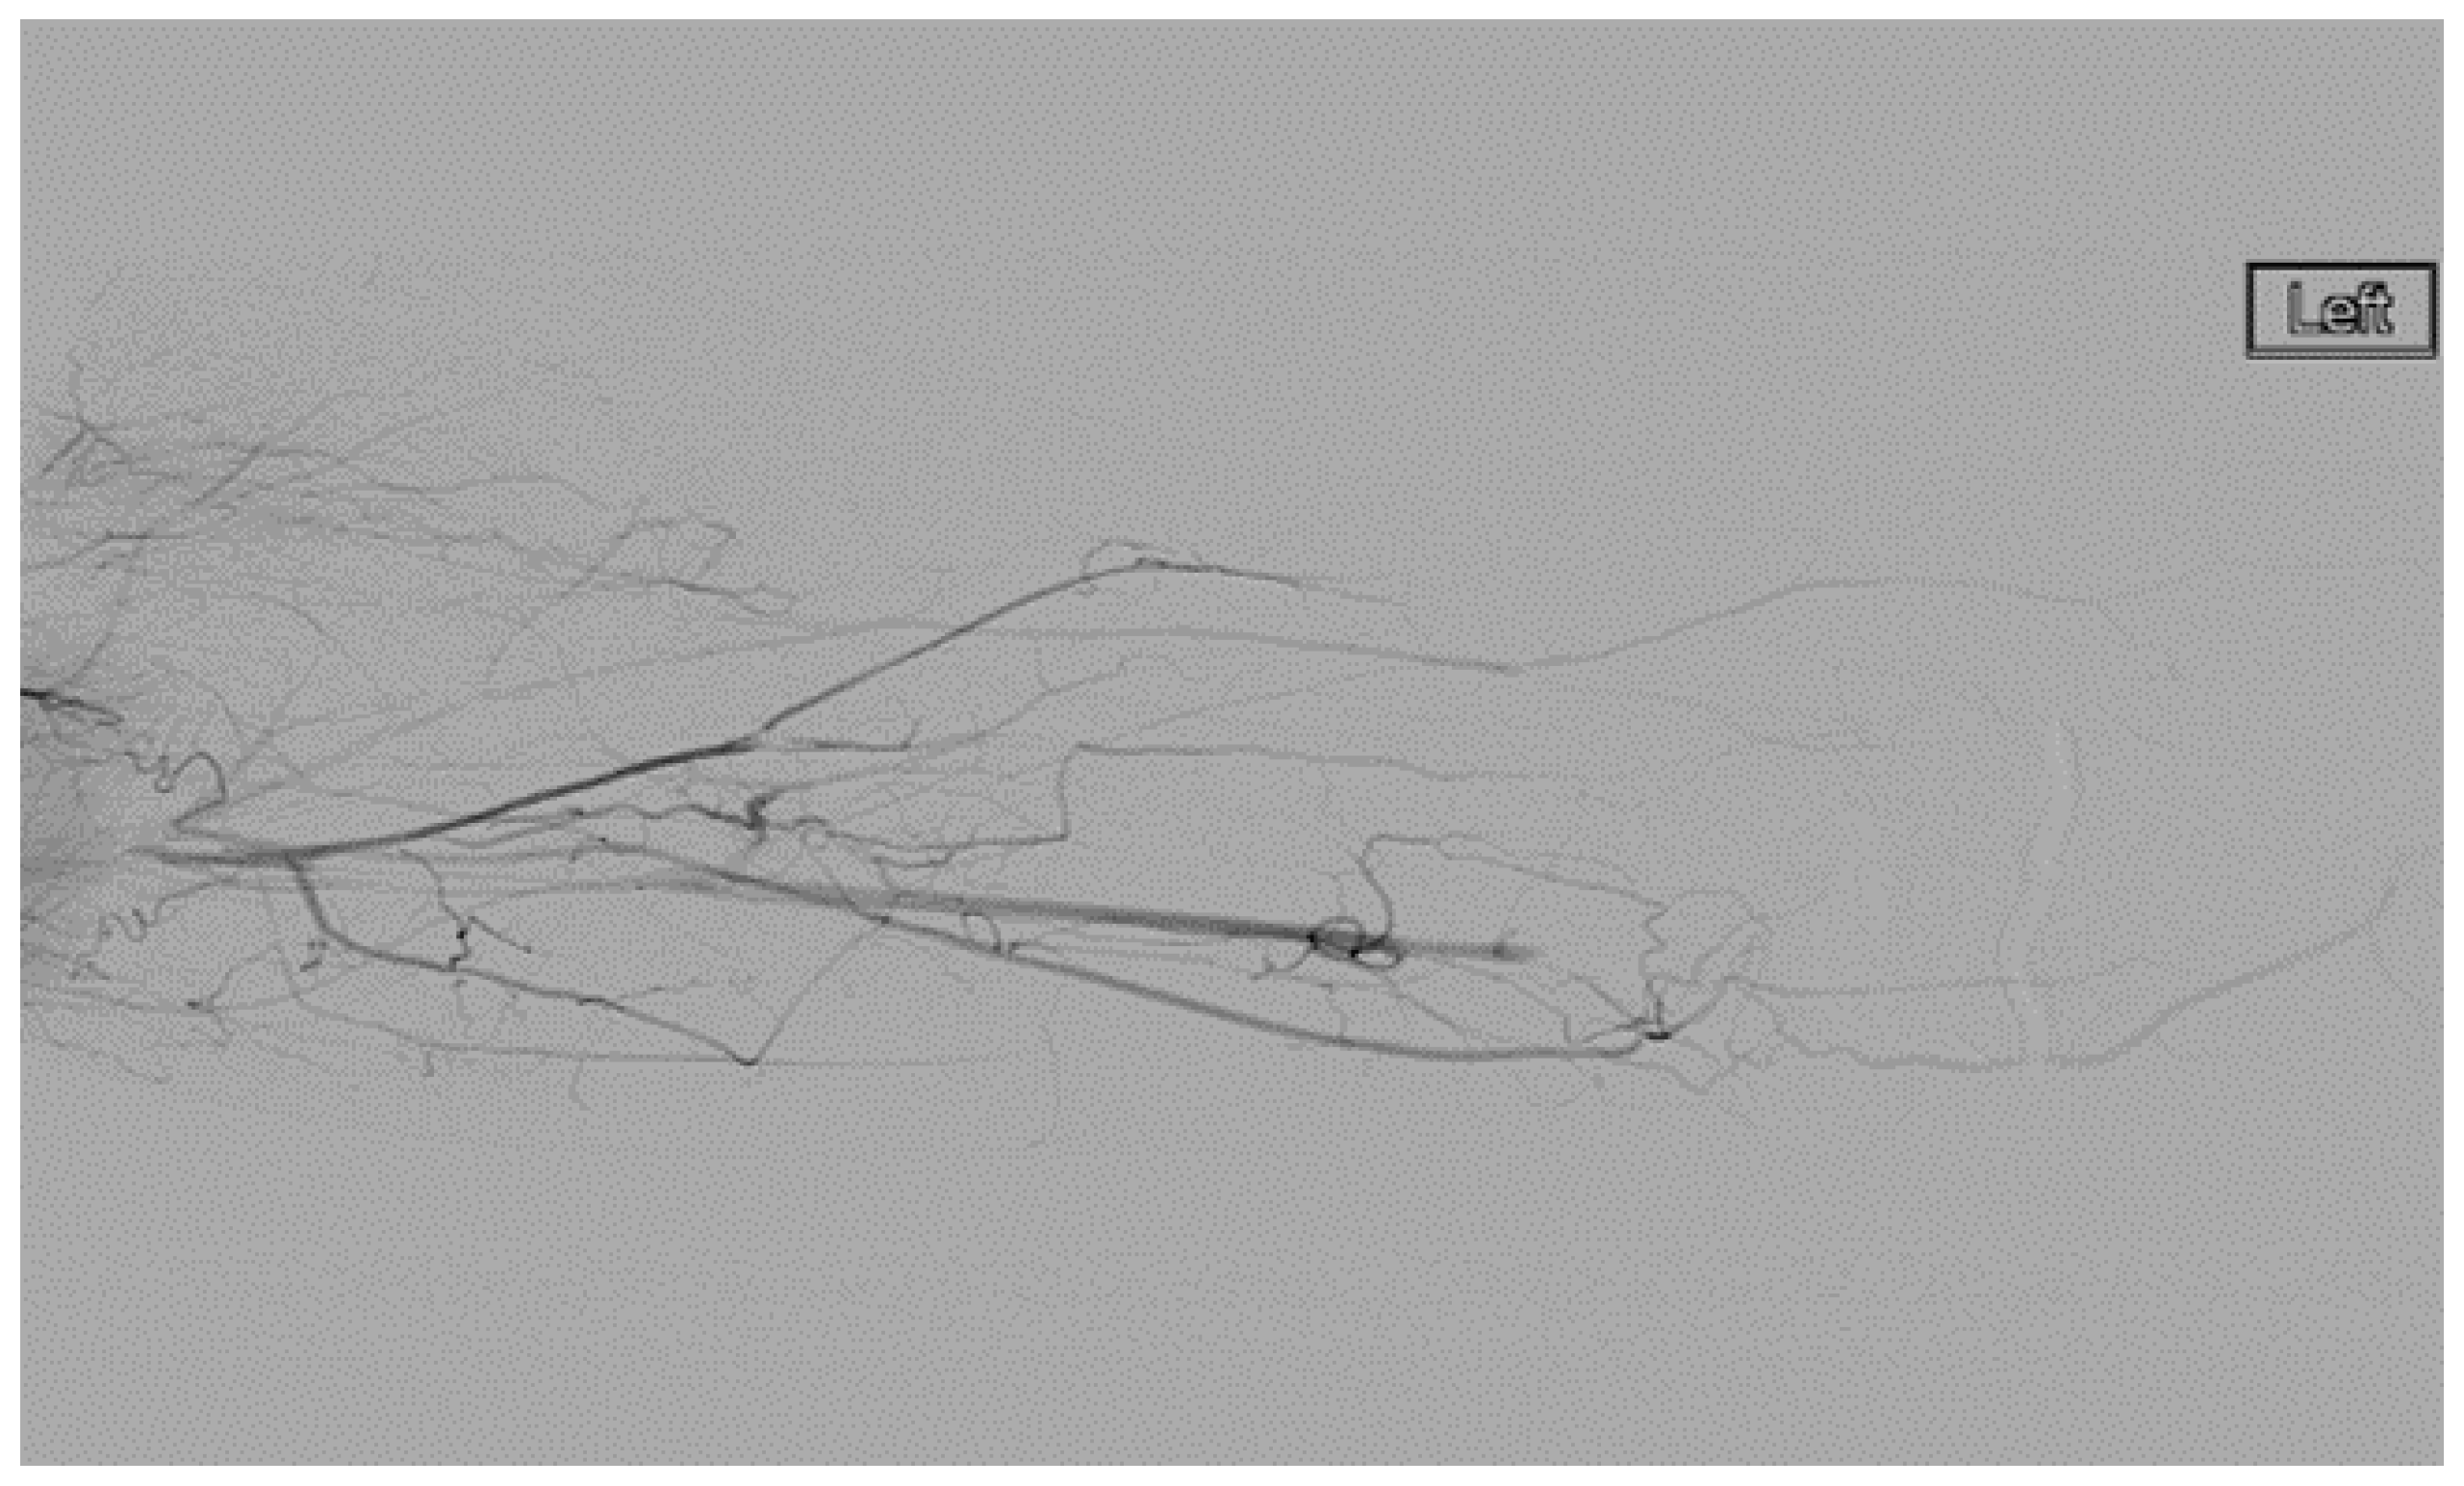

She underwent venography of the right arm venous system which revealed a 70–80% stenosis of the right subclavian vein in neutral position (Figure 1 and Figure 2). The vein was completely occluded in stress position. This was confirmed with intra-vascular ultrasound (IVUS). On IVUS measurements, the neutral position yielded a 74.4% stenosis while the stress position yielded 100% total occlusion (Figure 3 and Figure 4). It was noted that the contralateral vein appeared compressed in the costochondral space as well, though she was asymptomatic.

Figure 2.

Venogram demonstrating a right subclavian vein that is nearly occluded while in stress position.

She underwent trans-axillary first rib resection. She recovered quickly and was discharged two days post-operatively. She resumed Rivaroxaban on post-operative day 5. She was brought back for a post-operative venogram with IVUS two weeks post-operatively. This revealed a high grade stenosis of the subclavian vein at the thoracic outlet. The lesion was treated with a 12 mm diameter balloon, which was effective.

A left-sided venogram was performed simultaneously, which revealed high-grade stenosis of the subclavian vein at the thoracic outlet. She was brought back two months afterwards for a trans-axillary first rib resection given the significant compression on venography and IVUS. It is important to note that treatment of the contralateral side is not widely accepted. However, we opted to proceed after a thorough discussion with the patient regarding her alternatives. She was kept on anticoagulation one month post-operatively, then discontinued. She was followed for up to one year post-operatively with no recurrence of symptoms and full resolution of normal activity.